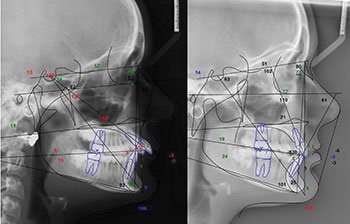

Evaluating the final records from outside-in, there were some noticeable facial changes worth noting. On profile, her lower one-third facial height increased (Figure 4) by way of clockwise rotation of her mandible (the SN-GoGN was increased from 16 to 24, shown in Figure 5). That vertical gain also permitted some other important esthetic improvements.

‘Short-Face’ Patients—Part 3

Fig. 4

Fig. 5